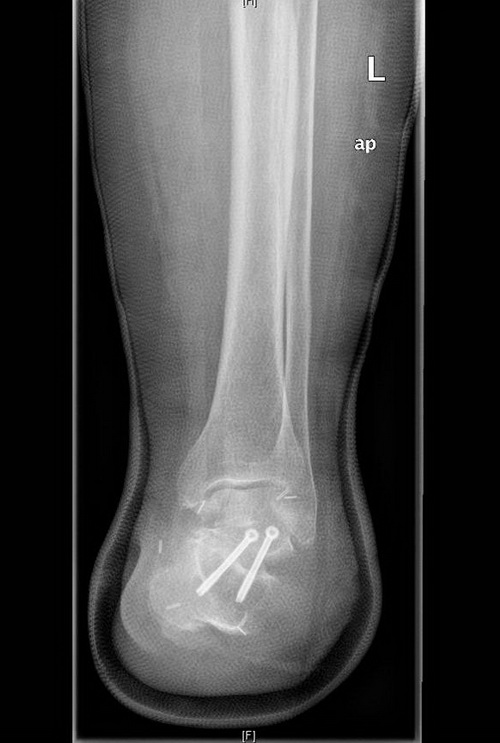

Postoperative Röntgenkontrolle: Linker Fuß in 2 Ebenen mit einer regelrechten Situation nach Amputation im Chopart-Gelenk im Bereich des Vorfußes. Darüber hinaus zeigen sich zwei einliegende Schrauben nach USG- Arthrodese. Kein Hinweis auf Impantatversagen oder Schraubenbruch.